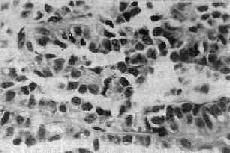

1.B细胞肿瘤 从胰岛B细胞(即B细胞)发生的肿瘤有腺瘤和腺癌;其中一部分能分泌胰岛素,可称之为insulinoma,临床上可有低血糖症状。大约80%是单发性腺瘤,10%为多发性腺瘤,10%是癌。本瘤可见于各个年龄层,但以40~50岁为多见。肉眼观,一般以胰体及胰尾部为多见,有完整包膜,大小为0.5~10cm,切面色微黄。组织学上,瘤细胞似胰岛细胞,呈多角形或柱状,胞浆颗粒状,细胞排列成条索或巢状,有时可出现菊形团排列。周围绕以血窦(图15-19)。间质中常出现淀粉样物质或钙盐沉积。其恶性者称为胰岛细胞癌。但由于肿瘤细胞常可因变性而出现多形性和奇异形核,因而从镜下区分良恶性有时也颇困难,常需根据其浸润性生长和淋巴结、肝转移等才能做出判断。

图15-19 胰岛细胞瘤